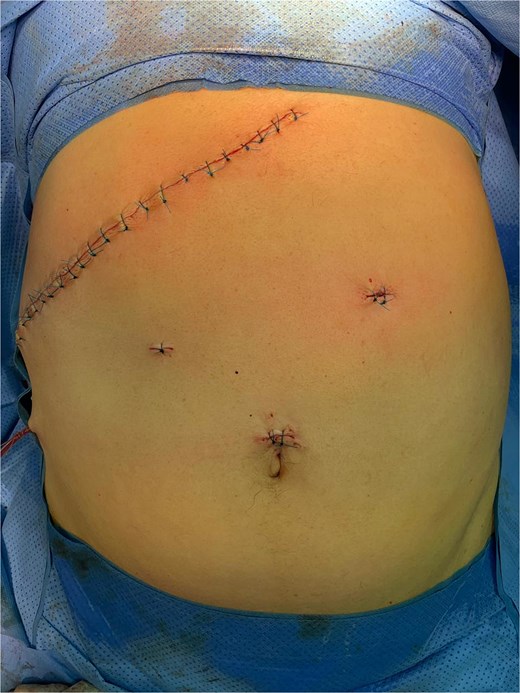

The initial laparoscopic approach was converted to right subcostal laparotomy (Fig. 2) due to unfavorable local conditions and severe inflammatory changes.

Surgical exploration revealed the true pathology: acute complicated cholecystitis with gallbladder fistulization to the subserosal gastric wall in the antro-pyloric region (Fig. 3), without mucosal involvement. The apparent ‘second gallbladder’ on imaging was actually a pseudocystic formation created by the fistulous communication and inflammatory process. The area was surrounded by significant inflammatory adhesions involving the omentum, creating a complex inflammatory mass.

Intraoperative view showing cholecystitis of a sclerotic and atrophic gallbladder associated with a cholecysto-gastric fistula.